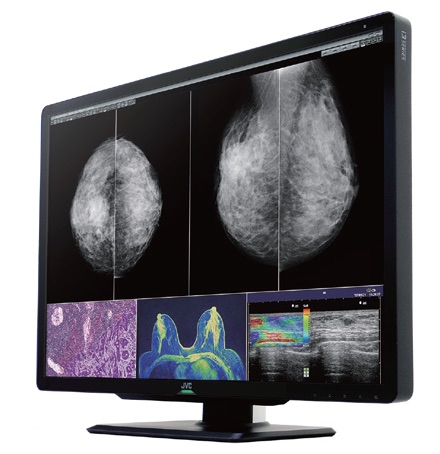

CL-S1200 液晶モニター

30.9型のワイドな画面領域かつ業界最高水準の1,200万画素(水平4,200x垂直2,800)の高解像度を実現し、マンモグラフィ画像の2画面表示だけでなく、CT・MRI・超音波・病理などさまざまな画像を同時に表示でき、自由なウィンドウレイアウトを可能に。また、シームレスな画面は視線移動の負荷を軽減し、快適な画像診断環境を提供する。

また、ターボルミナンス機能により30秒間、画面輝度とコントラストを最大値まで引き上げ、識別できるグレースケール階調を拡大させ、低コントラストの病変を見つける必要があるマンモグラフィ画像診断に貢献する。

さらに、モニター背面に搭載されたRear Lightは、間接照明として目に優しい環境照度を提供。底面に搭載されたReading Lightは、手元にあるキーボードやマウスなどを照らす(ライトはどちらも明るさ調整可)。

画面の位置調整時など、手が触れる頻度が高い筐体部分に抗菌コーティングを施し、操作キー部については、簡単に貼り付けできる抗菌機能を持ったフィルムを付属することで、菌の増殖を防ぎ、感染リスクを軽減。

液晶面を低反射ガラスフィルターで覆い、凹凸や隙間の少ないノイズレスデザインを採用している。

業界最高水準※1となる高解像度1200万画素を実現するカラー液晶モニター「CL-S1200」

日本乳がん検診精度管理中央機構より「適合モニタ」として認定を受けた本製品は、マンモグラフィ画像の二画面表示だけ でなく、CT・MRI・超音波・病理など、さまざまな医用画像を一台で同時に表示でき、自由なウィンドウレイアウトを可能にする。さらに手が触れる頻度が高い筐体部分には抗菌コーティング※2を施し、菌の増殖を防ぎ、感染リスクを軽減できる。

※1: 放射線画像診断で利用される医用モニターとして(2020年11月時点、当社調べ)。

※2: 全ての菌に対して抗菌効果を有するわけではありません。抗菌コーティングはスタンドおよびガラスフィルターを除きます。